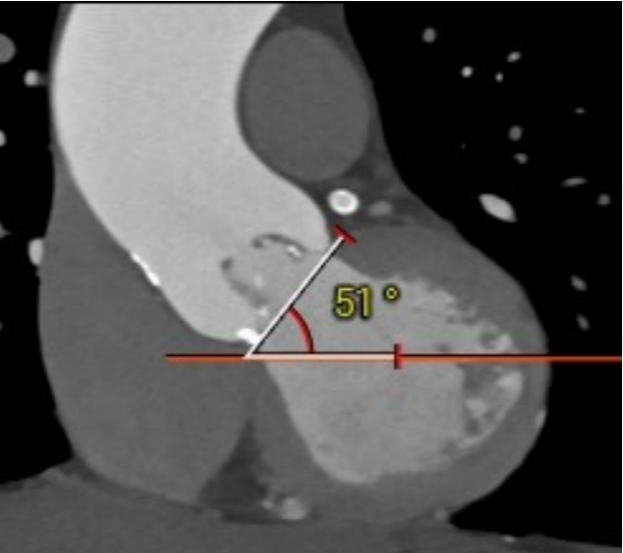

心室角度51度: